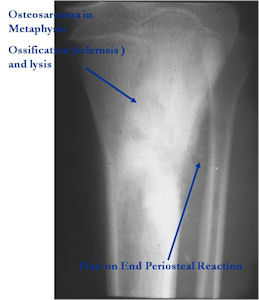

Aggressive Osteoblastoma vs. Osteosarcoma

Osteosarcoma:

- Cellular atypia

- High mitotic rate

- Atypical mitotic figures

- Abundant lacelike osteoid

- Permeative growth into adjacent bone and soft tissue

- Presence of neoplastic cartilage

- No peripheral shell of reactive bone

- Osteoblastomas that are greater than 4 cm and that show prominent periosteal new bone formation may present problems in differentiation from osteosarcoma

- May have foci of lace-like osteoid, high cellularity and more than a few scattered mitotic figures but these characteristics usually occur independently in an osteoblastoma vs all these atypical characteristics being present in an osteosarcoma